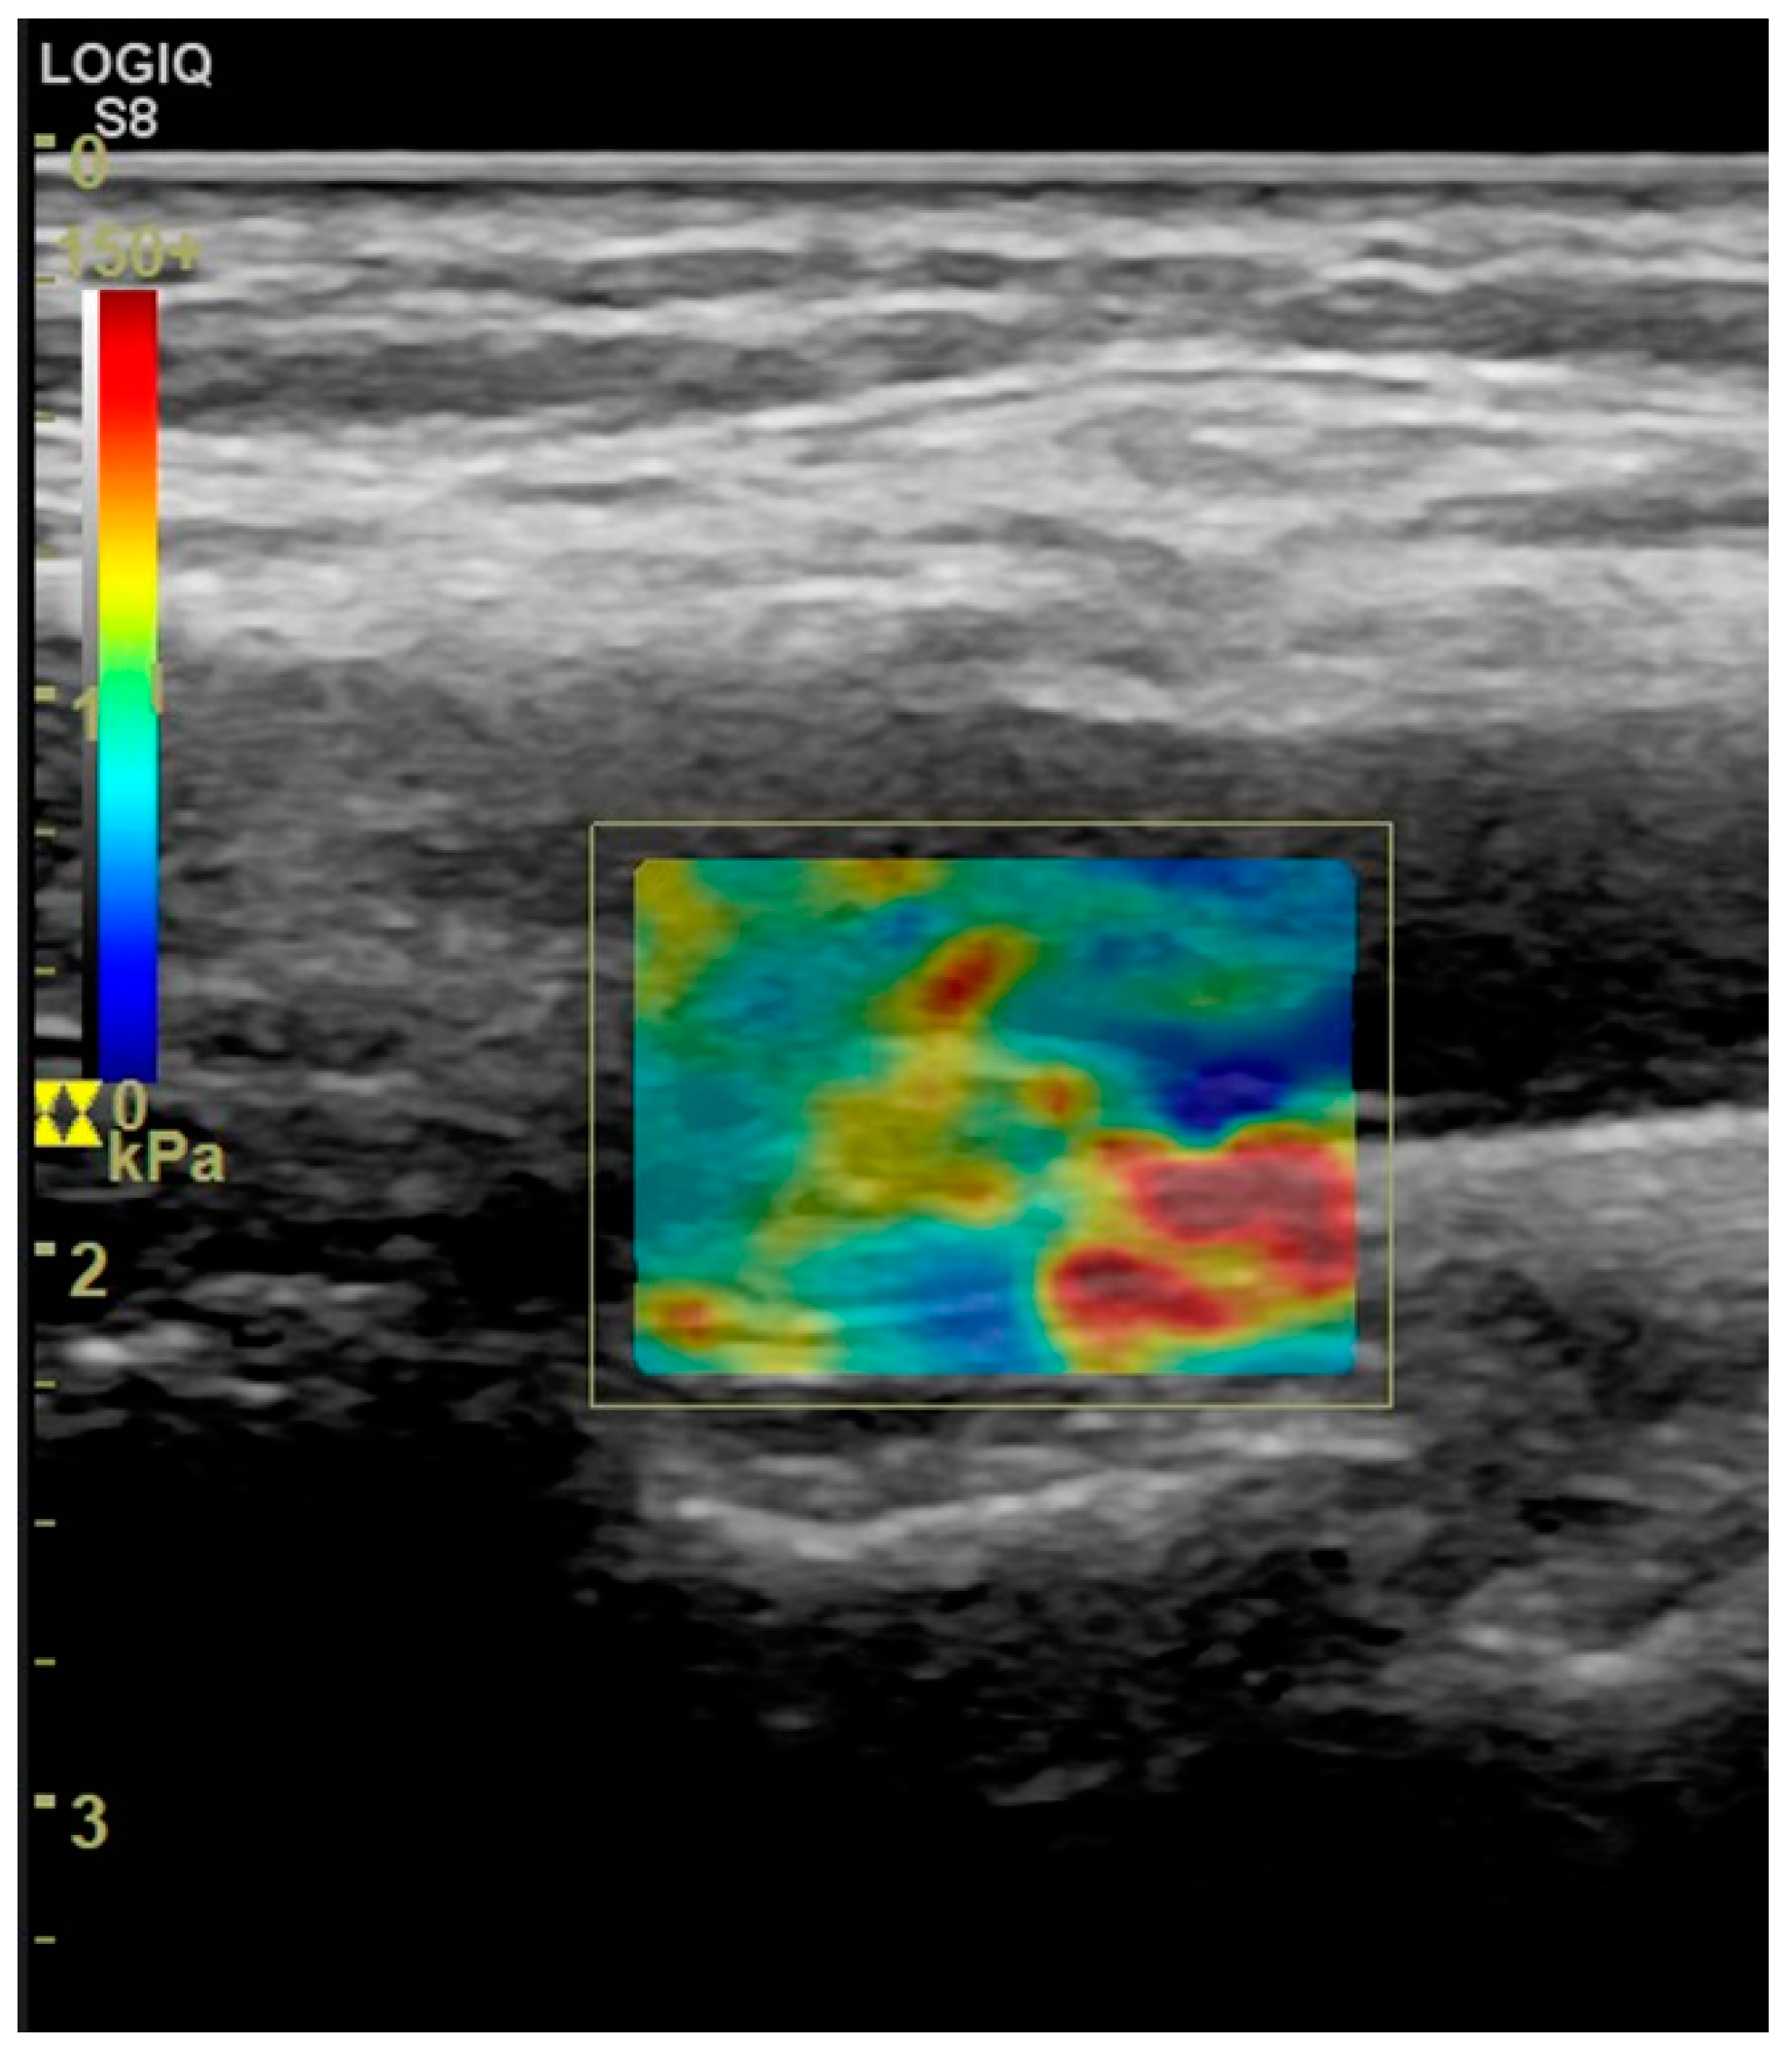

- Di Leo, N.; Venturini, L.; de Soccio, V.; Forte, V.; Lucchetti, P.; Cerone, G.; Alagna, G.; Caratozzolo, M.; Messineo, D.; Di Gioia, C.; et al. Multiparametric ultrasound evaluation with CEUS and shear wave elastography for carotid plaque risk stratification. J. Ultrasound 2018, 21, 293–300. [Google Scholar] [CrossRef]

- Liu, F.; Yong, Q.; Zhang, Q.; Liu, P.; Yang, Y. Real-Time Tissue Elastography for the Detection of Vulnerable Carotid Plaques in Patients Undergoing Endarterectomy: A Pilot Study. Ultrasound Med. Biol. 2015, 41, 705–712. [Google Scholar] [CrossRef]

- Lou, Z.; Yang, J.; Tang, L.; Jin, Y.; Zhang, J.; Liu, C.; Li, Q. Shear Wave Elastography Imaging for the Features of Symptomatic Carotid Plaques: A Feasibility Study. J. Ultrasound Med. 2017, 36, 1213–1223. [Google Scholar] [CrossRef]

- Ramnarine, K.V.; Garrard, J.W.; Kanber, B.; Nduwayo, S.; Hartshorne, T.C.; Robinson, T.G. Shear wave elastography imaging of carotid plaques: Feasible, reproducible and of clinical potential. Cardiovasc. Ultrasound 2014, 12, 49. [Google Scholar] [CrossRef]

- Garrard, J.W.; Ummur, P.; Nduwayo, S.; Kanber, B.; Hartshorne, T.C.; West, K.P.; Moore, D.; Robinson, T.G.; Ramnarine, K.V. Shear Wave Elastography May Be Superior to Greyscale Median for the Identification of Carotid Plaque Vulnerability: A Comparison with Histology. Ultraschall Med. 2015, 36, 386–390. [Google Scholar] [CrossRef]